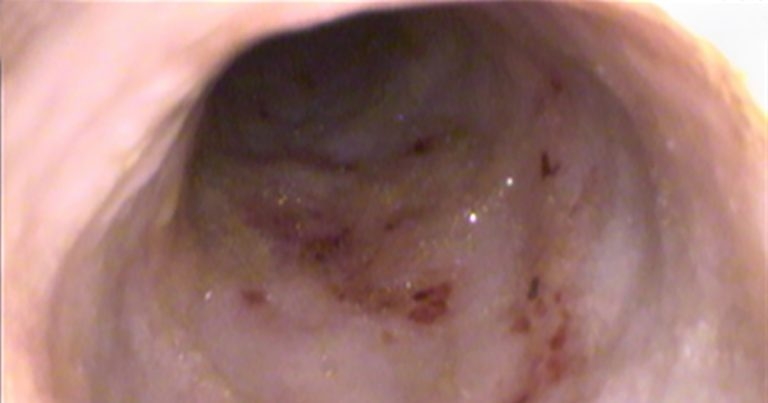

Endoscopic picture of the duodenum showing multiple superficial ulcers in a dog that presented with anaemia without macroscopic evidence for gastrointestinal bleeding.

Occult faecal blood has been used in the past in cases of anaemia for which GI bleeding is suspected, but no macroscopic evidence exists (no haematochezia or melaena), or imaging evidence of any underlying cause (such as the description of an ulcer). However, this test is not very practical, as a specific diet (hydrolysed or vegetarian) has to be fed for few days, and it is not considered the most reliable test in general1.

Some cases where the author has used endoscopic capsules are cases of anaemia or GI bleeding that, after an extensive work-up, an obvious cause has not been found, and it can be useful to confirm the origin of the problem. Sometimes, endoscopy confirms the lesion, and the capsule is not placed to save costs (Figure 6).

It is important to bear in mind that even if ultrasound does not show any ulcers, it does not mean none are present, as the sensitivity of ultrasound has been reported to be low for non-perforated ulcers13.